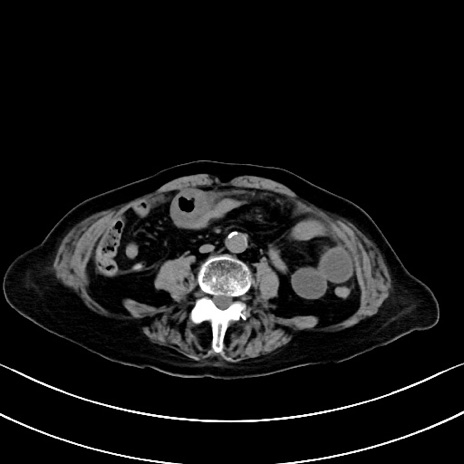

横断像

他院CT